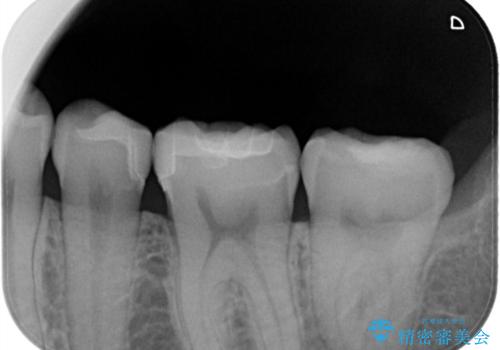

- 主訴:銀の詰め物が取れた、奥の銀の詰め物も一緒に白くしたい

保険適用のメタルインレーの脱離で来院されました。審美性、適合性、清掃性の観点から2本ともセラミックインレーでのやり替えとなりました。

保険適用のメタルインレーはセラミックやゴールドに比べるとプラークなどの汚れが付きやすく、また今回はそこまで大きなう蝕は広がっていませんでしたが、適合性に限界があるためインレーと歯質との境目で二次う蝕が発生する可能性が高くなります。